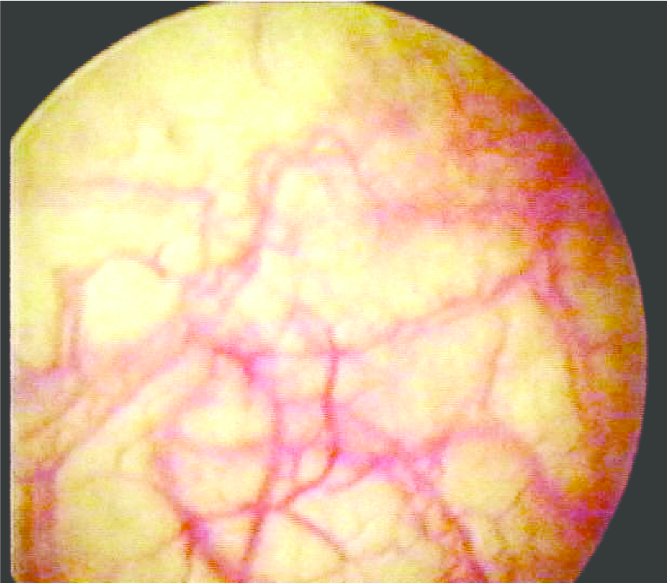

📍 A review of cystoscopy showed hyperemia.

@rkalyes1 @TSM_Humanist @ChefKarim02 @DrOribaDan @DrAkhilX @drkeithsiau @DrRobertsen @Drwafulafrnco @SemitalaFred @ACCESS_UG @ps_lukwago Schistosoma Hematobium, the first normal cystoscopy made us think Nutcracker Syndrome. Praziquantel is excellent but ineffective against immature schistosomes but also some studies showing treatment with Praziquantel especially for S.Hematobium.